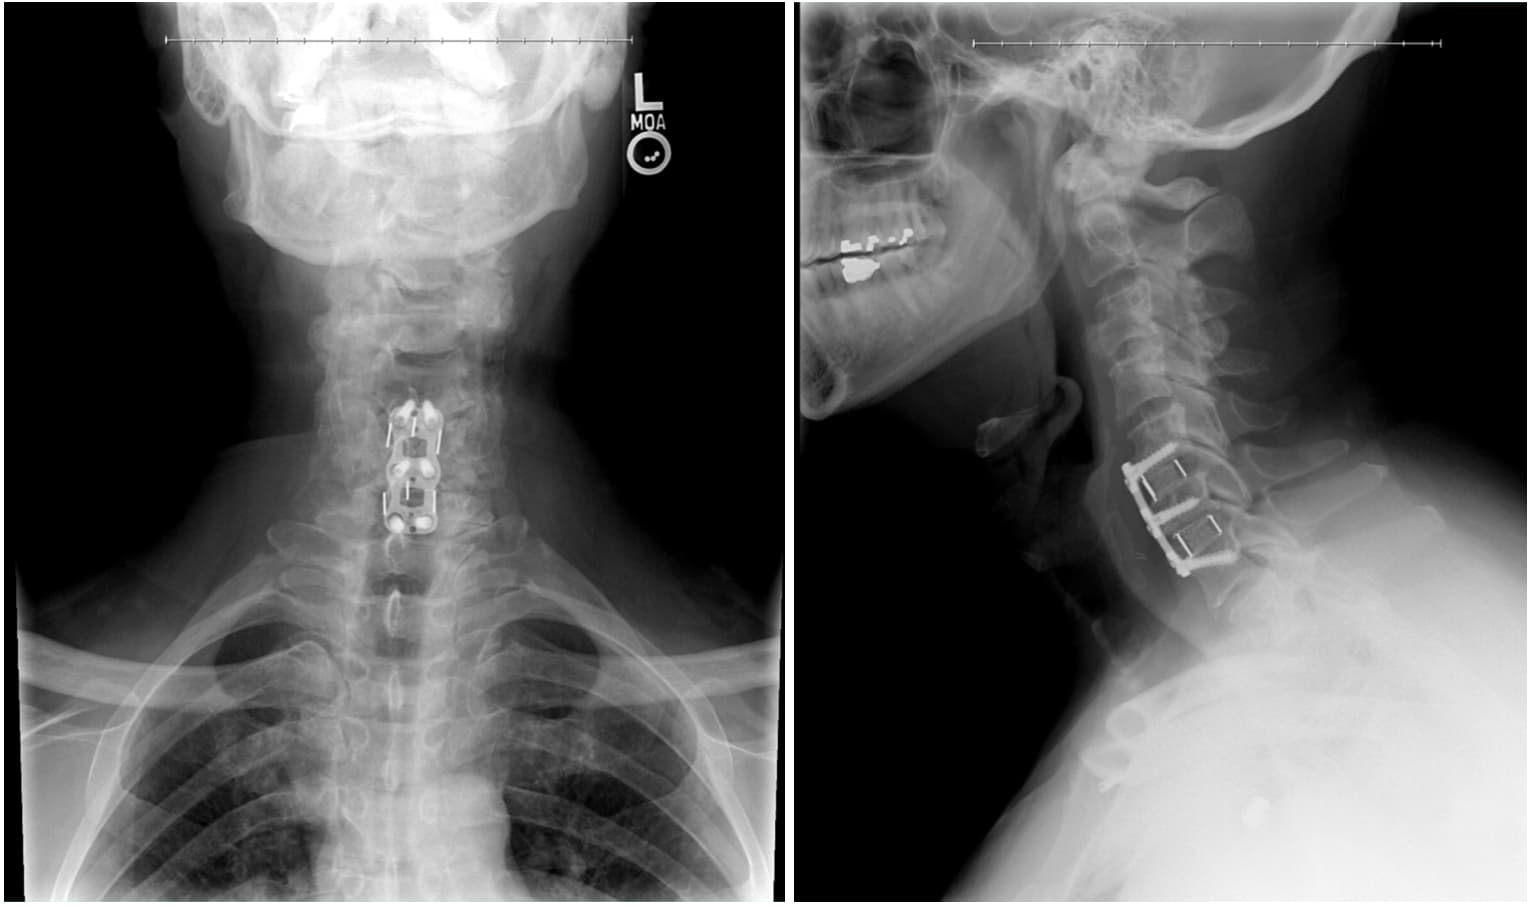

They took the X-rays posted above to check that everything looked right and released in the late afternoon.